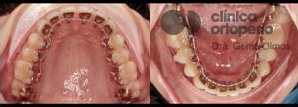

¿Cómo quedan los dientes con brackets?